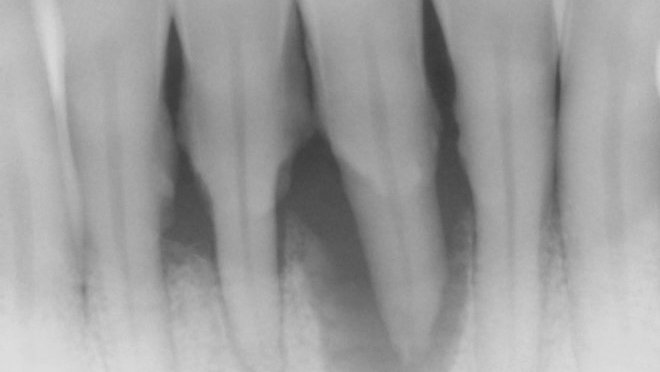

- Ensure tooth does not have a root fracture and check/refer for endodontic treatment if tooth is nonvital (figure 1)

- Splint tooth and adjust occlusion11 (figure 2)